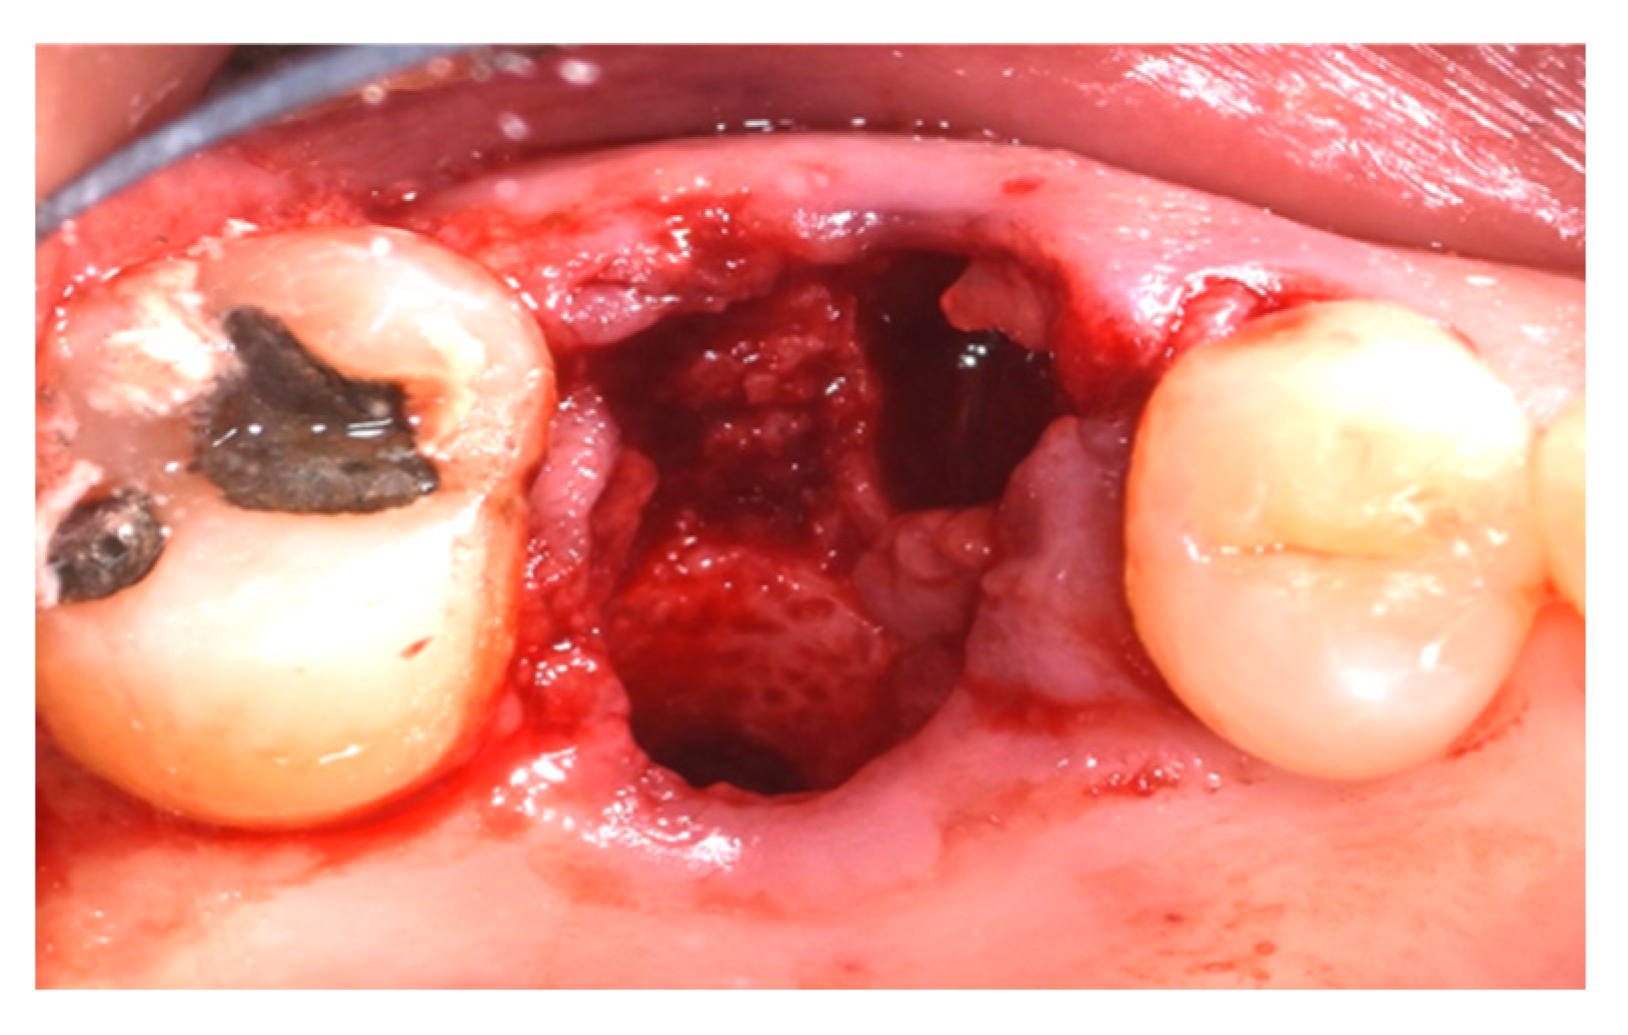

2.4. Surgical Procedure, Evaluation at Follow-Up, and Collection of Radiographic Data